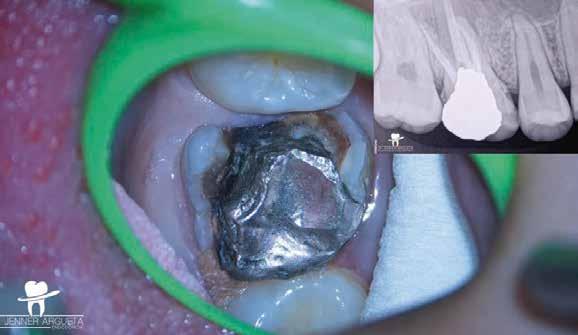

1. a–f ábrák: A cingulumon keresztül gömbfúróval kialakított hozzáférés a trepanációs kavitás labiális irányba történő túlzott mértékű kiterjesztését eredményezheti, és ez lényegesen növelheti a perforáció esélyét (a). A guttapercha átsejlik a lágyrészek alatt (b). Klinikailag igazolt perforáció (c). A preoperatív sagittális irányú CBCT-szeleten jól látható a labiális perforáció (d). Labiális irányú perforáció (fekete nyíl; e). A tényleges gyökércsatorna (piros nyíl; f).

2. a-b ábrák: A cingulumon keresztül gömbfúróval végzett trepanálás túlzott pericervikális dentin áldozattal, fordított tölcsér effektussal és perforációk kialakulásával járhat (fehér nyíl).

A frontfogakban történő hozzáférési nyílás kialakítása

A frontfogakban a hozzáférési nyílás kialakítását hagyományosan a fogak linguális vagy palatinális felszínén, a cingulumon keresztül egy gömbfúró segítségével kezdjük. A linguálisan elhelyezkedő kiemelkedés teljes eltávolítása, továbbá a pulpaszarvak teljes feltárása egy háromszög alakú hozzáférési nyílást eredményez. 7 Ezt a módszert a fogak esztétikai megjelenésének megőrzése érdekében fejlesztették ki. Ez azonban időnként a saját foganyag indokolatlan eltávolításával, a trepanációs kavitás labiális irányba történő túlzott kiterjesztésével, perforációval, valamint a fog kritikus helyen, a pericervikális dentin (PCD) területén történő meggyengítésével jár (1. a–f és 2. a-b ábrák). 19 Felmerült, hogy a pericervikális dentin rendkívül fontos szerepet játszik a rágóerő gyökerek irányába történő továbbításában, és elképzelhető, hogy a gyökérkezelt fogak hosszú távú megtartása szempontjából a legfontosabb tényező az ép pericervikális dentin megőrzése lehet. 20 A cingulumon keresztül történő hozzáférési nyílás